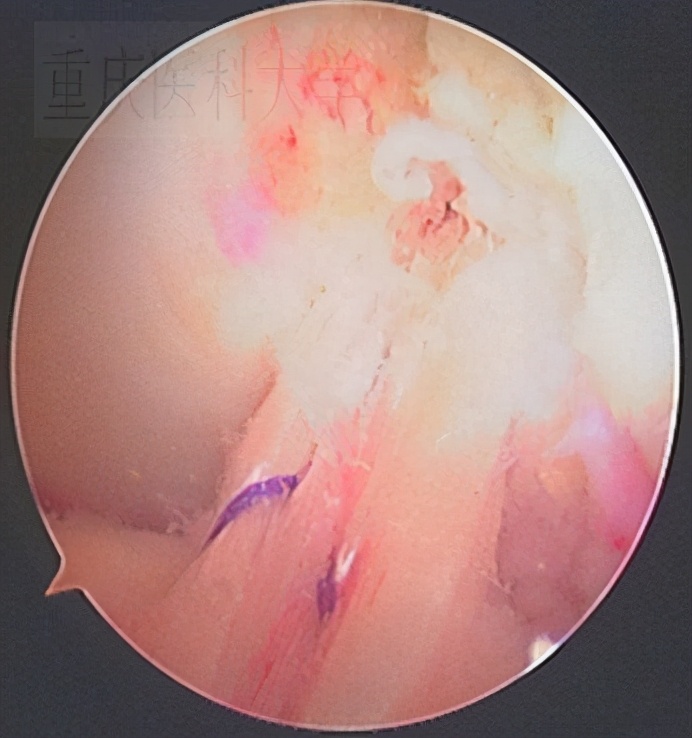

1.前交叉韧带损伤 目前主流做法是取自体腘绳肌肌腱解剖单束重建或双束重建,材料也可选用同种异体材料或人工肌腱。要根据损伤的类型,患者活动情况,年龄,经济状况等综合考虑。

单束重建术后的前交叉韧带: